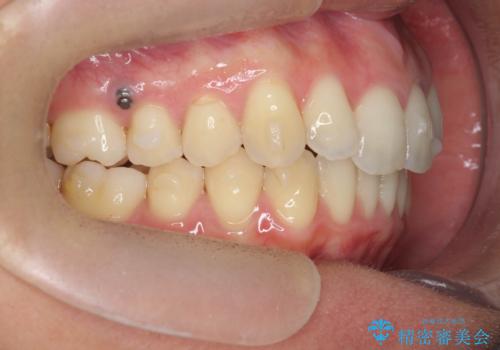

過蓋咬合・上顎前突・叢生を改善するマウスピース矯正

- 前歯のがたつき、不揃いさの改善を求めて来院されました。

・前歯の深い噛み合わせ (過蓋咬合)

・上顎前突(Angle Class2)

・叢生(がたつき)

以上のような問題点をマウスピース矯正インビザラインとマイクロインプラントを用いて矯正治療を行い改善して行きます。